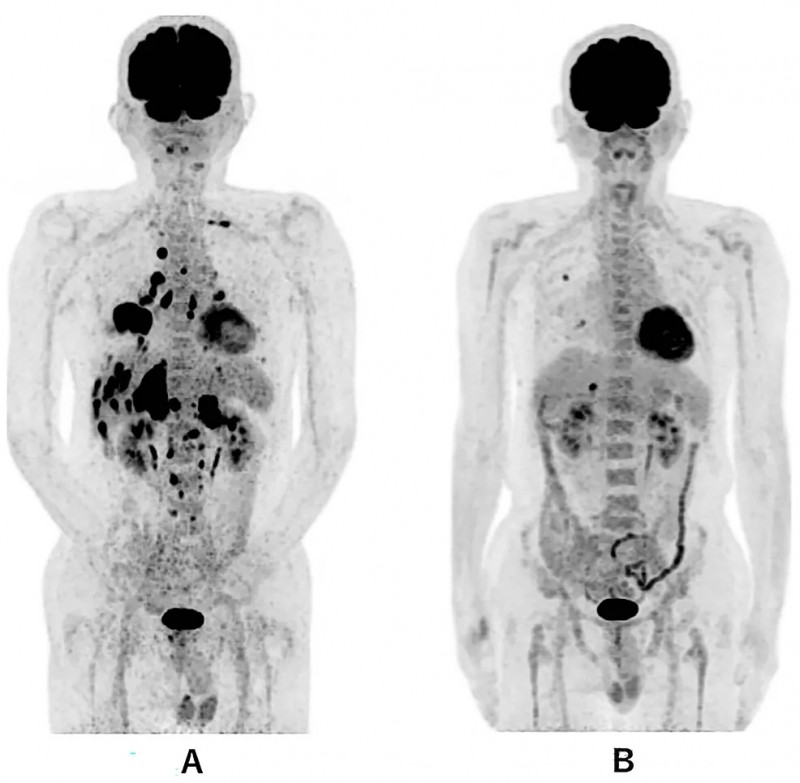

权威医学期刊《Cureus》曾记录过一个堪称经典的案例:一位69岁的Ⅳ期肺鳞癌患者,已经出现了双侧肾上腺、肝脏、骨骼的广泛转移,一线化疗复发,命悬一线。

在启动了WT1-DC疫苗联合多西他赛及靶向药治疗后,奇迹发生了:无进展生存期(PFS)超过了577天!不仅肺部原发灶缩小了70%以上,全身的转移灶也出现了显著的消退。 肿瘤标志物断崖式下降,患者的体力恢复,能够重新回归正常生活。疫苗极大地优化了患者的免疫微环境,延长了化疗的有效窗口期。